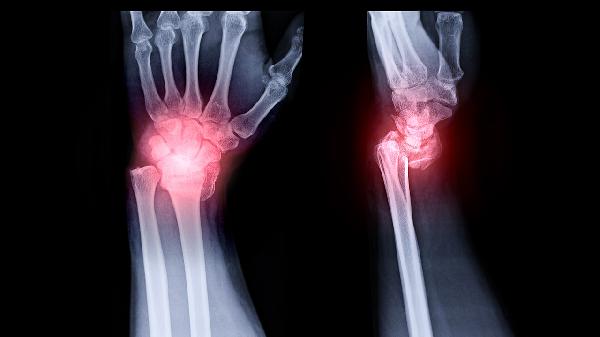

2、关节病变评估

通过X线可观察关节间隙变化、骨质增生和关节面破坏等情况,对骨关节炎、类风湿关节炎等关节病变具有重要诊断价值。膝关节、髋关节等承重关节的X线检查能显示软骨下骨硬化、骨赘形成等特征性改变。